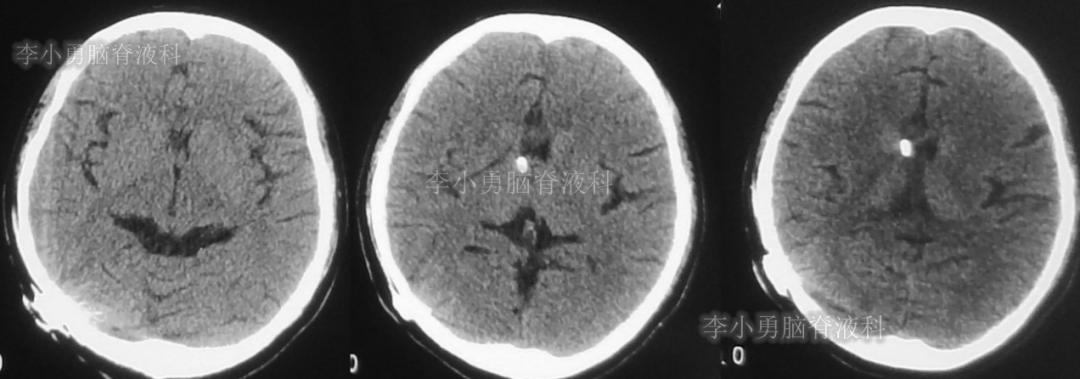

此后1个多月(2019年11月4日到2019年12月16日),患者意识一直无改善,一直呈模糊状态,多次复查头颅CT(图-12至图-20)见脑室大小反复变化不定,医生根据CT结果等反复多次调节分流泵压力(具体过程家属回忆不起)。但患者病情无好转却逐渐加重,逐渐不能咀嚼、吞咽及进食,卧床不起。

图-12:2019年11月8日头颅CT

图-13:2019年11月16日头颅CT

图-14:2019年11月19日头颅CT

图-15:2019年12月3日头颅CT

图-16:2019年12月10日头颅CT

图-17:2019年12月12日头颅CT

图-18:2019年12月13日头颅CT

图-19:2019年12月14日头颅CT

图-20:2019年12月16日头颅CT